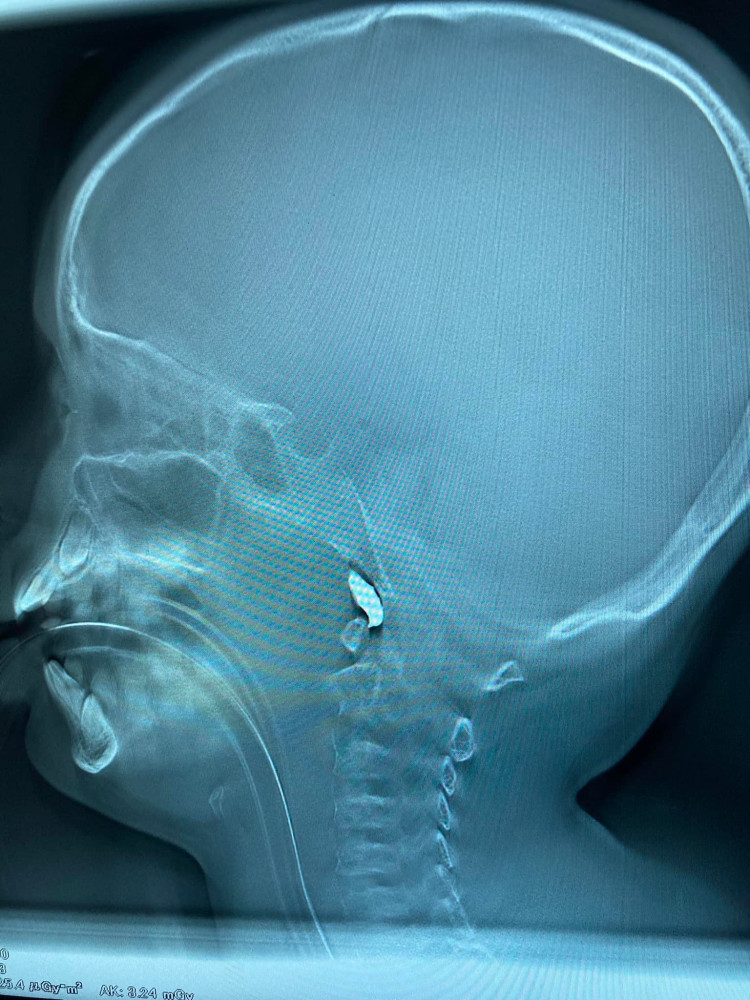

В Харькове врачи спасают десятилетнего мальчика: в его голову попал осколок снарядаХарьковские врачи борются за жизнь десятилетнего мальчика. Во время вражеского обстрела в голову ребенка попал осколок снаряда . «Еще один мальчик 10 лет. Минновзрывное. Снаряд влетел в помещение. Работаем», — пишет врач Александр Духовский. СМЕРТЬ РОСІЙСЬКИМ ОКУПАНТАМ! Помітили помилку? Виділяйте слова з помилкою та натискайте control-enter |